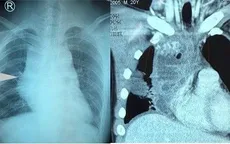

VTV.vn - Bệnh viện Bãi Cháy (Quảng Ninh) vừa phẫu thuật nội soi cắt trọn u trung thất sau kích thước lớn, nằm sát cột sống và màng phổi bệnh nhân.

VTV.vn - Người bệnh đi khám xương khớp vì bị đau cột sống thắt lưng, tê bì 2 chân nhưng sau đó lại phát hiện khối u trung thất lớn kích thước 12x7cm.

VTV.vn - Bệnh viện Trung ương Thái Nguyên vừa mổ thành công cắt bỏ khối u quái trung thất kích thước 13 x 8 x 7 cm cho người bệnh nữ 38 tuổi.

VTV.vn - Bệnh viện đa khoa tỉnh Thanh Hóa vừa phẫu thuật khối u nặng gần 8kg trong lồng ngực nam bệnh nhân 56 tuổi.

VTV.vn - Khoa Phẫu thuật tim - Lồng ngực mạch máu, Bệnh viện Nhân dân 115 vừa phẫu thuật lấy khối u trung thất thành công cho nam bệnh nhân 20 tuổi ở Đồng Nai.

VTV.vn - Bệnh viện Bãi Cháy (Quảng Ninh) vừa phẫu thuật nội soi lồng ngực lấy khối u trung thất khổng lồ cho bệnh nhân Đoàn Văn N.